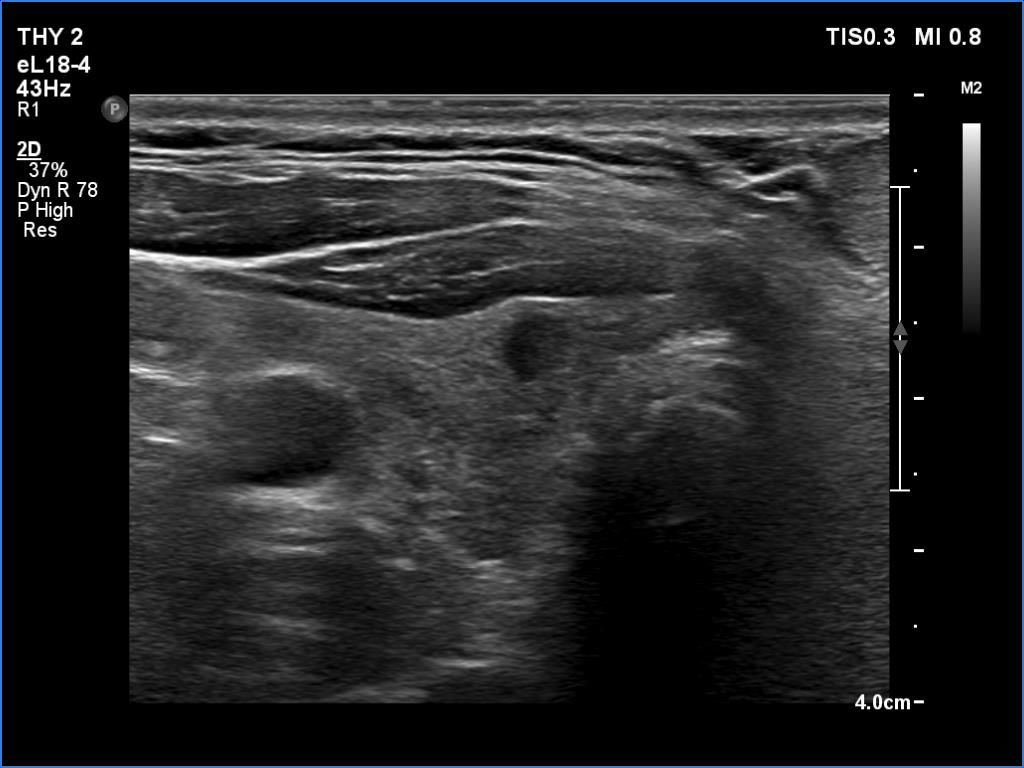

Clinical data: A 49-year-old man requested evaluation of a neck mass which was discovered by the patient himself while shaving.

Ultrasonography. The thyroid was echonormal and had several small cystic lesions without any clinical or oncological importance. According to the palpable mass, a moderately hypoechoic lesion was detected several centimeters under the thyroid in the middle of the neck. The lesion was within the muscle tissue. It was homogeneous and presented no vascularity.

Aspiration cytology of the lesion resulted in lipoma.